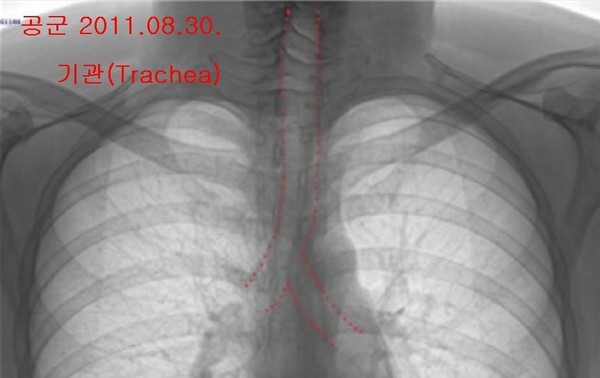

- ▲ 박주신씨 명의 엑스레이(위로부터 공군·자생). 기관의 주행 형태를 볼 수 있다. ⓒ 의료혁신투쟁위원회

특히 남 전 교수는 “피사체의 고개를 돌리거나 꺾는 등 자세를 바꾼 상태에서 촬영을 해도 기관의 모양은 변하지 않았다”며, 촬영방식이나 호흡법, 자세 때문에 기관의 방향이 다르게 보일 수 있다는 주장은 납득하기 어렵다고 설명했다.남 전 교수는 엑스레이를 해부학적 관점에서 분석한 결과, 촬영 당시 호흡상태의 차이에도 불구하고, 흉곽 모양은 크게 차이가 나지 않는다는 점도 확인할 수 있다고 덧붙였다.

감정 대상이 된 주신씨 명의의 엑스레이는 ①자생병원 엑스레이(2011년 12월 9일), ②공군훈련소 엑스레이(2011년 8월 30일), ③주신씨가 영국 출국에 앞서 비자발급을 위해 세브란스병원에서 촬영한 엑스레이(2014년 7월 31일) 등 3장이다.

<차> 공군과 비자 엑스레이 피사체의 기관은 안쪽(오른쪽)으로 굽은 형태, 자생 엑스레이 피사체의 기관은 곧은(직진) 형태로 나온다. 그런데 증인은 이런 차이가 나타나는 원인을, 촬영 자세와 호흡의 차이 때문이라고 설명했다.

<증> 촬영 자세나 호흡이 다르면 충분히 저런 변화가 관찰될 수 있을 것으로 생각했다.